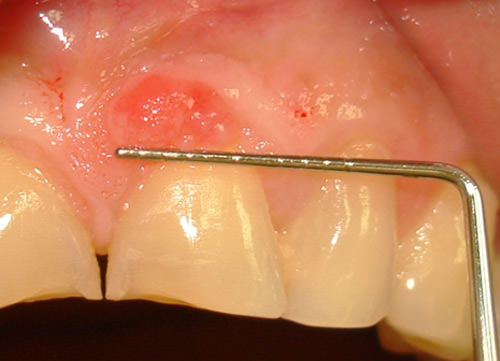

El paciente presenta al examen clínico una lesión en la encía marginal, por vestibular del 21, de forma ovoide (figura. 1), con 5 mm de diámetro (figura. 2), consistencia blanda, textura rugosa, base sésil, color rojizo, crecimiento lento e indoloro, y de 18 meses de evolución.

Fig. 1

Granuloma Piógeno

Fig. 2

Granuloma Piógeno. Lesión de 5mm aproximadamente